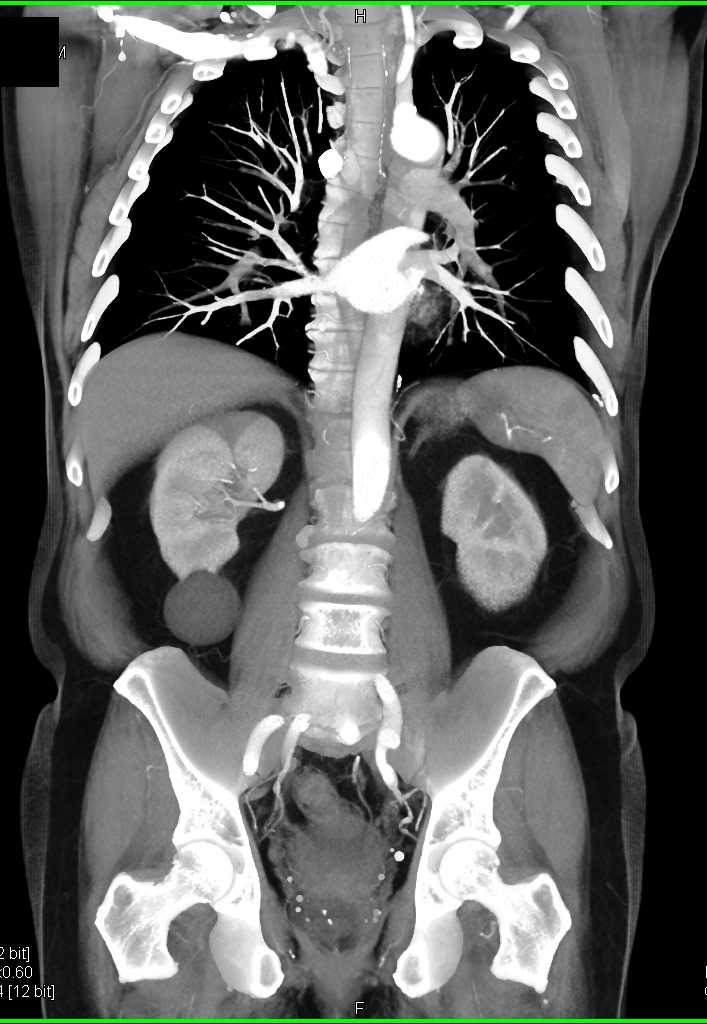

Acute Pyelonephritis Right Kidney